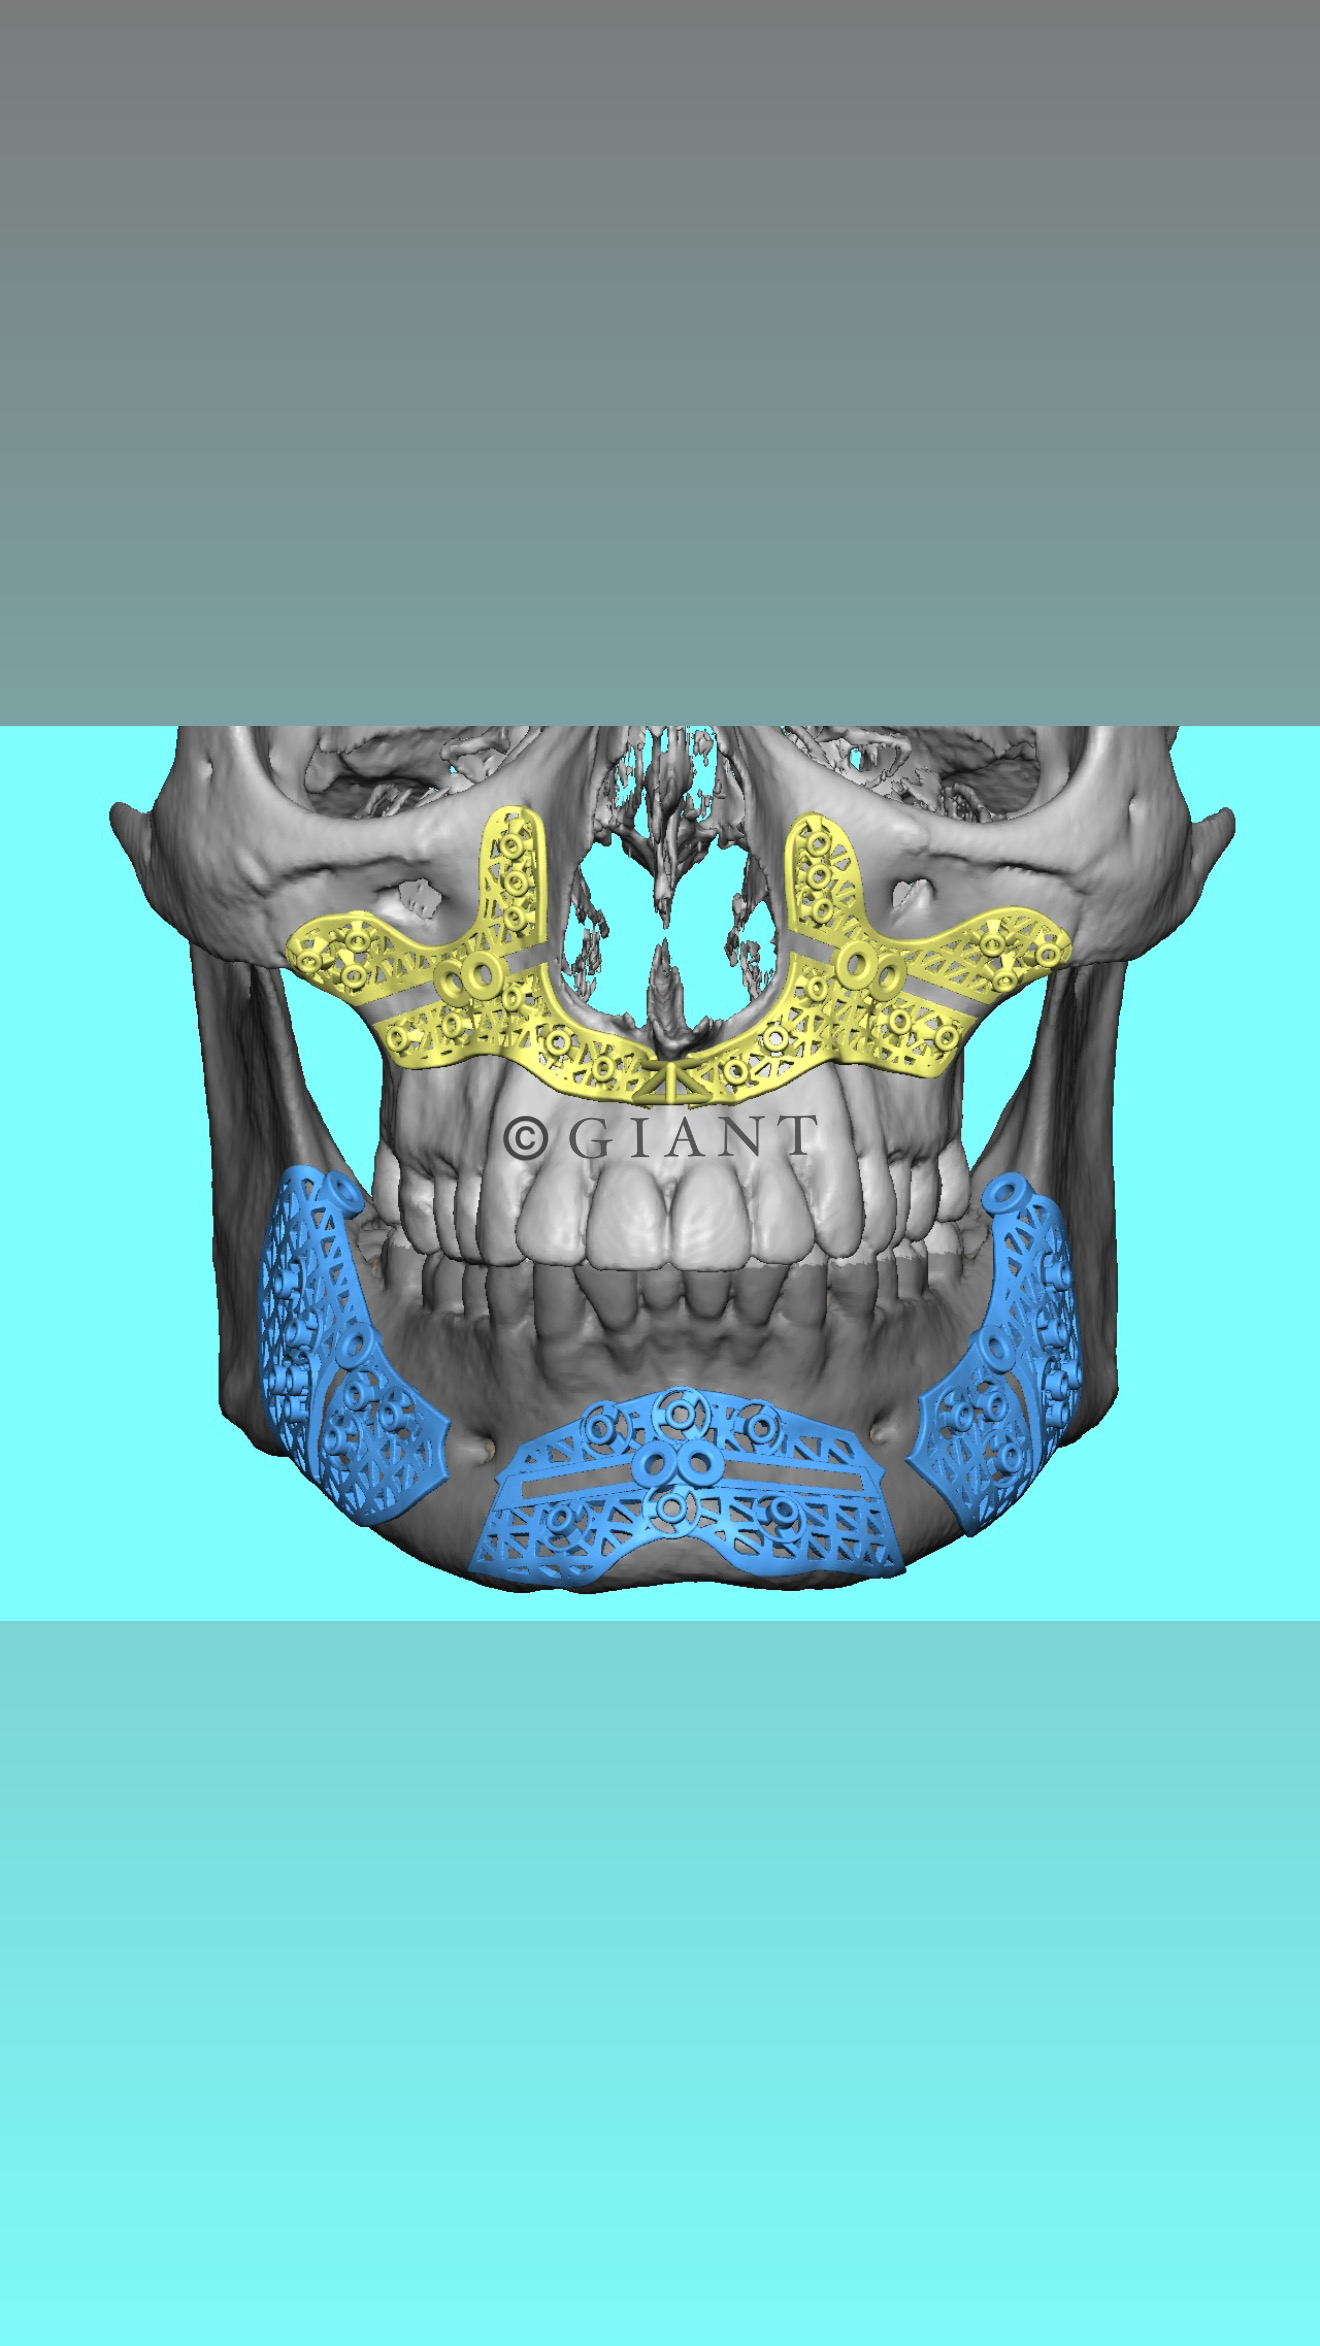

Why do surgeons like Gunson shit on custom guides and plates in the mandible? Something about not being able to predict the optimal joint position or something like that. Are they just coping and unwilling to do the extra planning required?It's annoying when people do that, because then im getting a subpar base to work on. I always wish they came for the full thing so I am not limited. Its supposed to all work together.

And no, I will not check or approve an external plan.

Because they're old dogs. Good at doing it the old fashioned way I will admit.Why do surgeons like Gunson shit on custom guides and plates in the mandible? Something about not being able to predict the optimal joint position or something like that. Are they just coping and unwilling to do the extra planning required?

but it's true that they are not reliable all the times thoBecause they're old dogs. Good at doing it the old fashioned way I will admit.

But this is the future.

View attachment 4222068View attachment 4222073